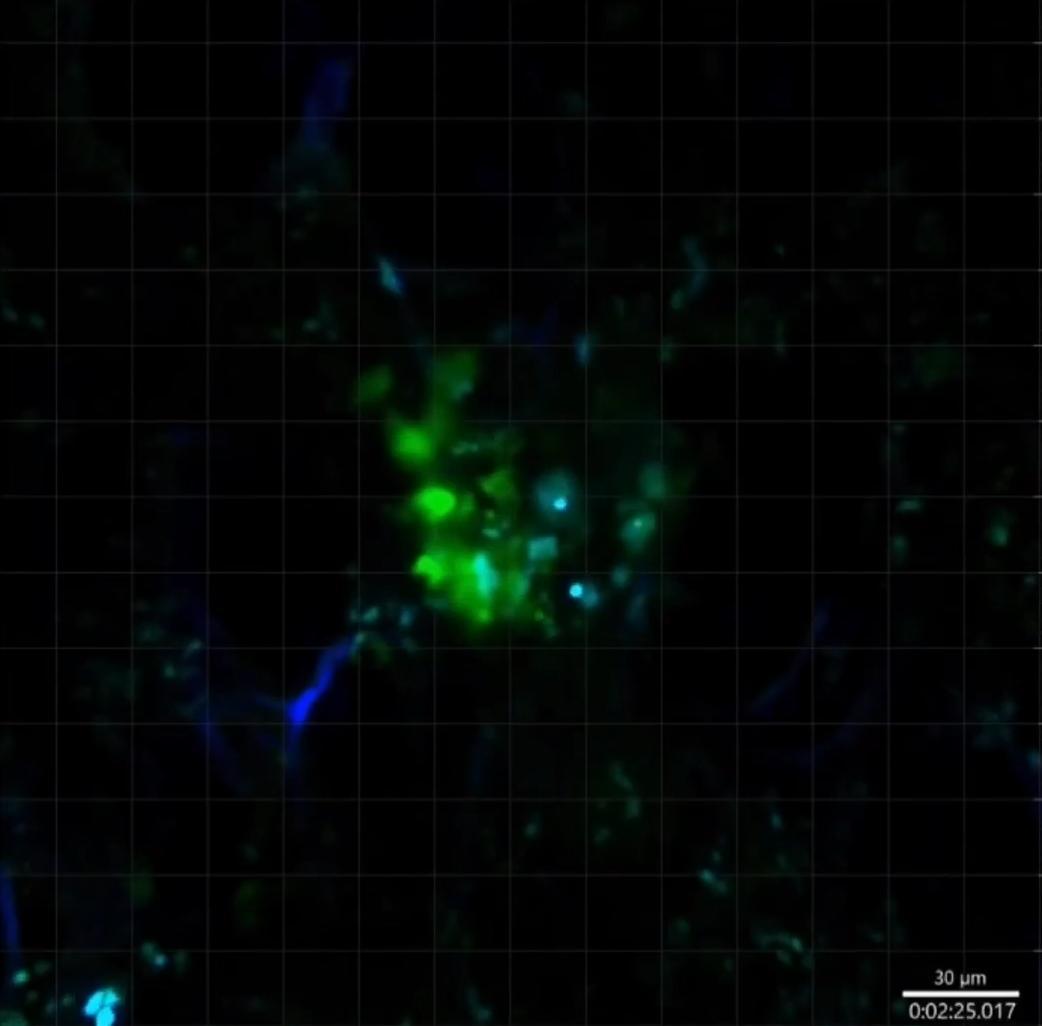

之後他們很快找到了答案:原來是一種叫做單核細胞的免疫細胞在發揮作用。這些細胞就像是人體內的特種部隊,通常負責巡邏和清除入侵者。

但在重症新冠感染期間,這支特種部隊獲得了新的"武器裝備"。病毒的遺傳物質(RNA)與這些細胞發生了獨特的互動,就像給了它們一個升級包,讓它們不僅能對付病毒,還能對付癌細胞。

他們首先分析了重症新冠患者的血液樣本, 然後在實驗鼠身上測試了四種不同類型的癌症,包括黑色素瘤、肺癌、乳腺癌、結腸癌等,結果令人振奮:通過藥物模擬新冠感染的免疫反應,這些實驗鼠體內的腫瘤確實開始縮小了!